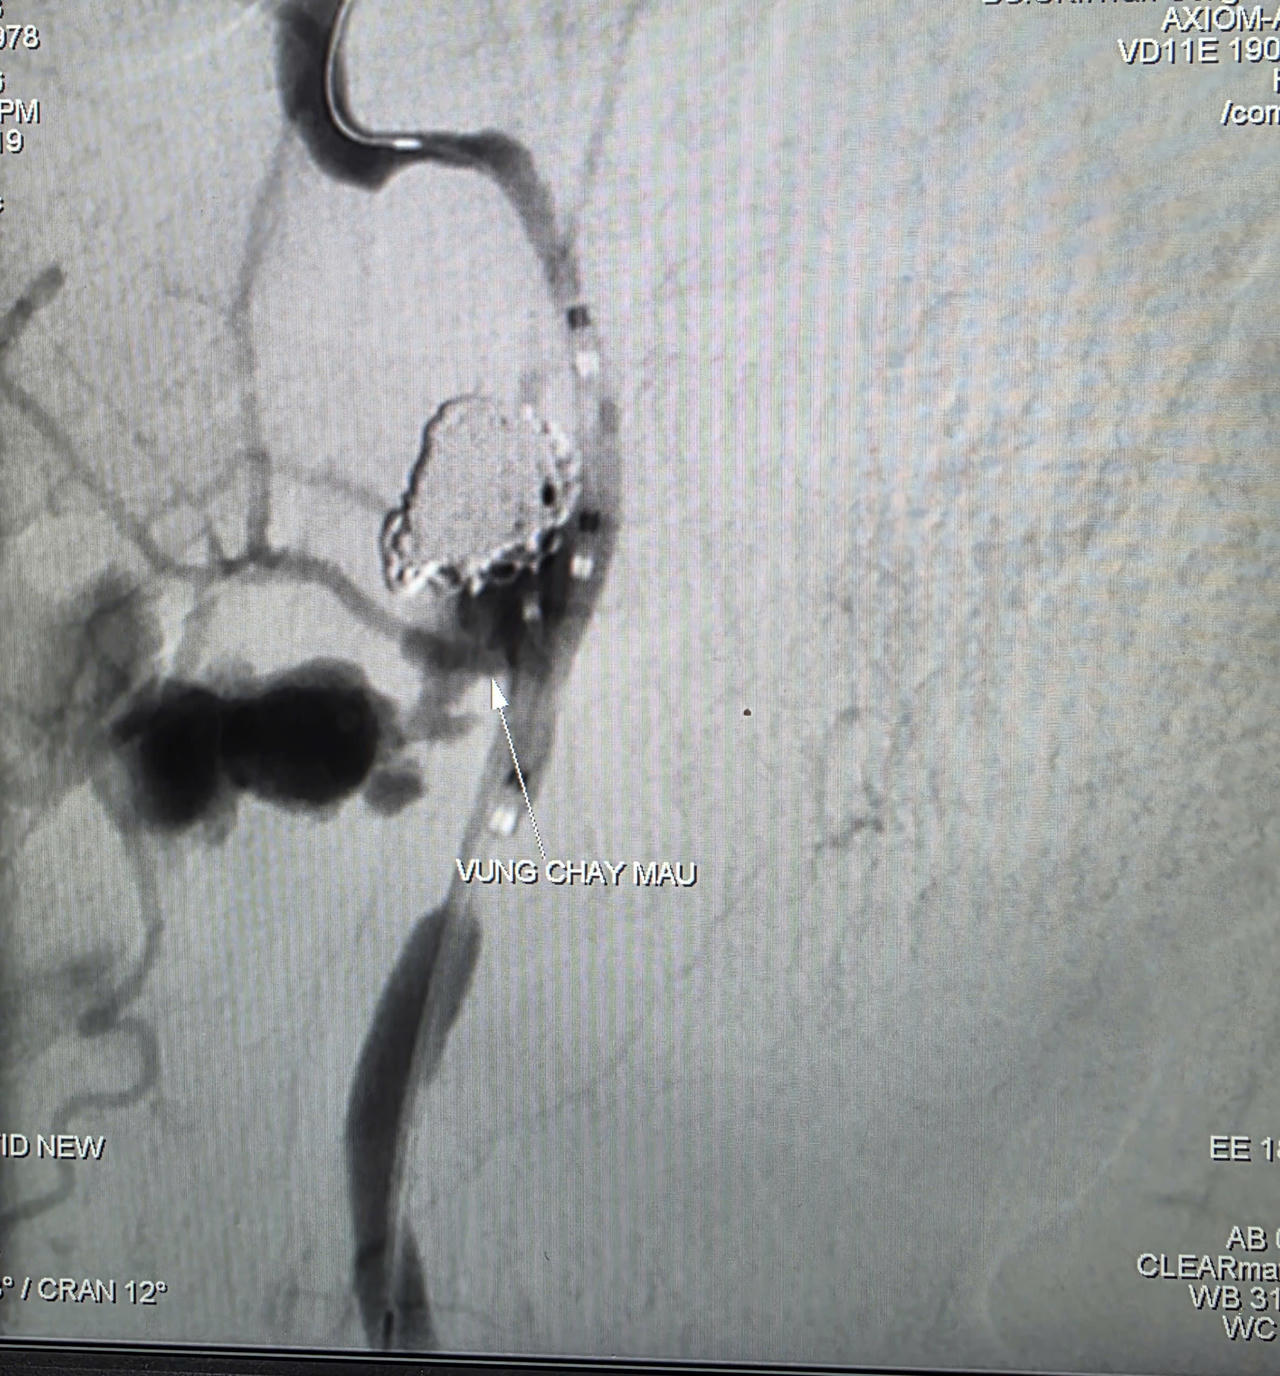

Các bác sĩ quyết định thực hiện chụp và can thiệp cầm máu dưới hệ thống chụp mạch số hóa xóa nền (DSA). Kết quả chụp mạch xác định ổ giả phình động mạch cảnh trong phải đoạn cổ, dưới nền sọ, kích thước khoảng 4,2 x 4,8 mm, cổ túi phình rộng và đang chảy máu.

Các bác sĩ đã dùng bóng chẹn dòng chảy kiểm soát lượng máu, sau đó luồn vi ống thông đến vị trí túi phình và thả 9 vòng xoắn kim loại (coils) để gây tắc hoàn toàn ổ giả phình và động mạch cảnh trong phải, qua đó kiểm soát triệt để nguồn chảy máu. Toàn bộ quá trình can thiệp kéo dài khoảng 90 phút. Đến ngày 6/3, bệnh nhân tỉnh táo, sức khỏe phục hồi khả quan.